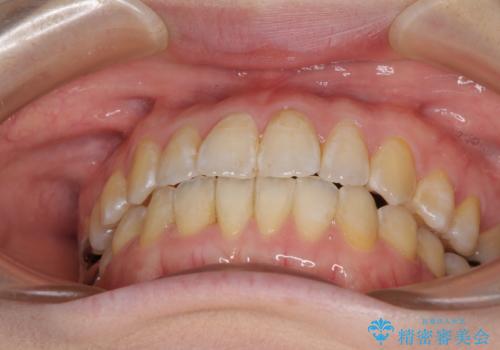

前歯のデコボコを治したい インビザラインによる矯正治療

- 前歯のデコボコを治したいとのことで来院された患者様です。

上下顎ともに歯列全体の後方移動とIPR(歯と歯の間を削る)によってデコボコが解消するように設計し、インビザラインにより治療を行うこととしました。

1日22時間の装着時間をほとんど達成することができず、治療には当初予定の2倍以上の期間を要することとなりました。